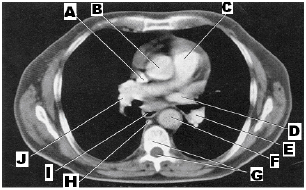

Entre as alternativas abaixo, qual apresenta uma estrutura que não está identificada na imagem, considerando que o corte axial ilustrado foi feito 1 cm abaixo da Carina?